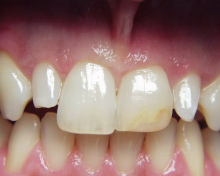

Auf diesem Foto sind die beiden vorderen

Schneidezähne Sichelzähne, "gekippte", "abgeknickte"

Zähne